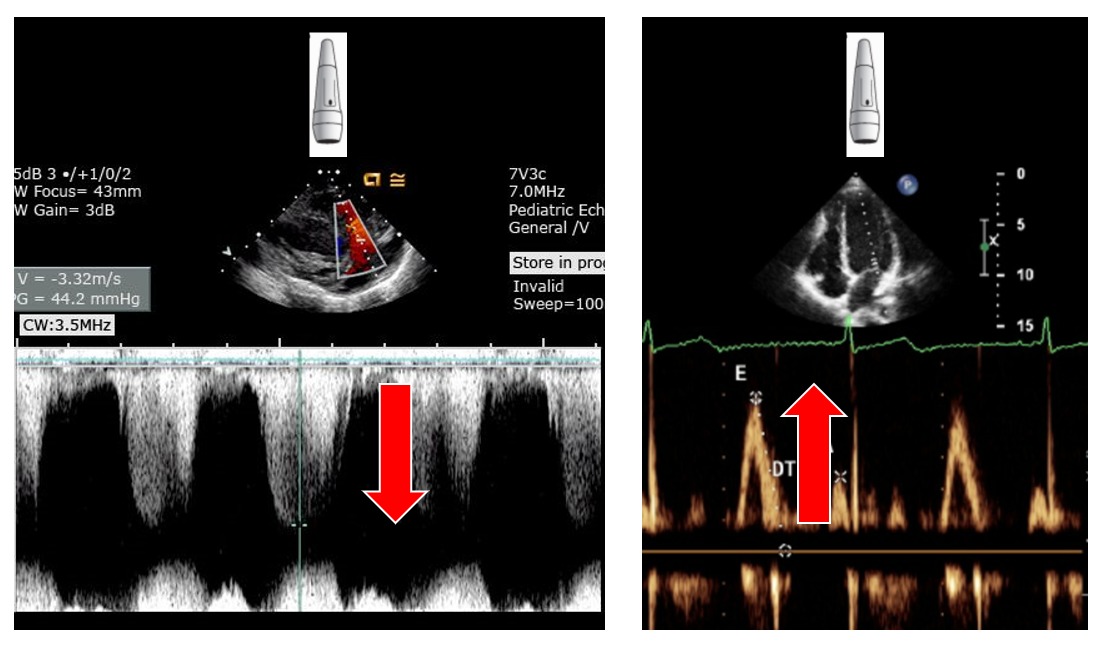

如果是認真要判斷的話請看圖片中0 m/s對應的那條水平線,以上的波型是靠近以下的是遠離探頭

基本上可以想像探頭就位於畫面的頂端

接著可以看波型尖端的指向與探頭是否指向同一方向

如左圖的波型就是在遠離探頭(指向圖片底端)、右邊的圖形就是在靠近探頭(指向圖片頂端)

以本圖來說,畫面中的波型就是指向圖片底端。代表血流方向為遠離探頭